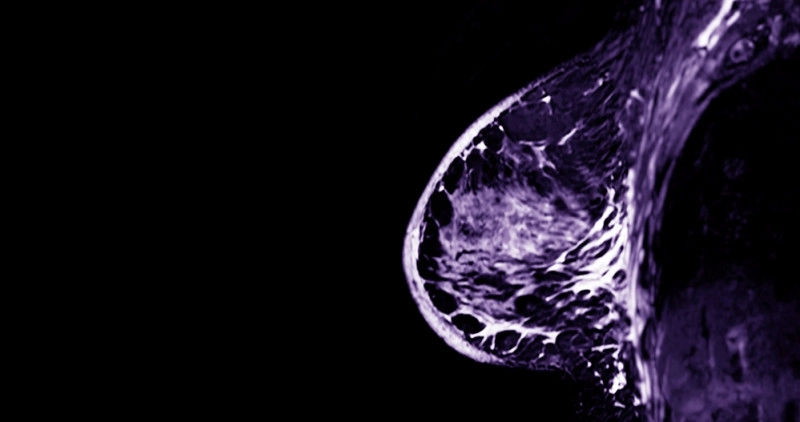

L’imagerie par résonance magnétique, plus connue sous le nom d’IRM, est un examen médical de plus en plus utilisé pour explorer les tissus du sein. Complémentaire à la mammographie et à l’échographie, l’IRM mammaire offre une vision très précise, notamment dans les cas complexes ou à risque élevé de cancer. Si l’idée de passer ce type d’examen peut susciter de l’inquiétude, savoir comment il se déroule permet souvent de mieux l’appréhender. Voici tout ce qu’il faut savoir pour s’y préparer sereinement.

L’IRM mammaire permet de visualiser les structures internes du sein avec une grande précision, grâce à des images en coupe obtenues par un champ magnétique. Elle est particulièrement utile pour détecter des lésions non visibles à la mammographie, en particulier chez les femmes aux seins denses.

L'IRM mammaire est un examen d'imagerie qui utilise un champ magnétique pour obtenir des images détaillées des tissus internes du sein. Elle permet de détecter avec précision des lésions non visibles à la mammographie, surtout chez les femmes ayant des seins denses, et est utilisée pour le diagnostic, le suivi ou la recherche de récidive du cancer du sein.